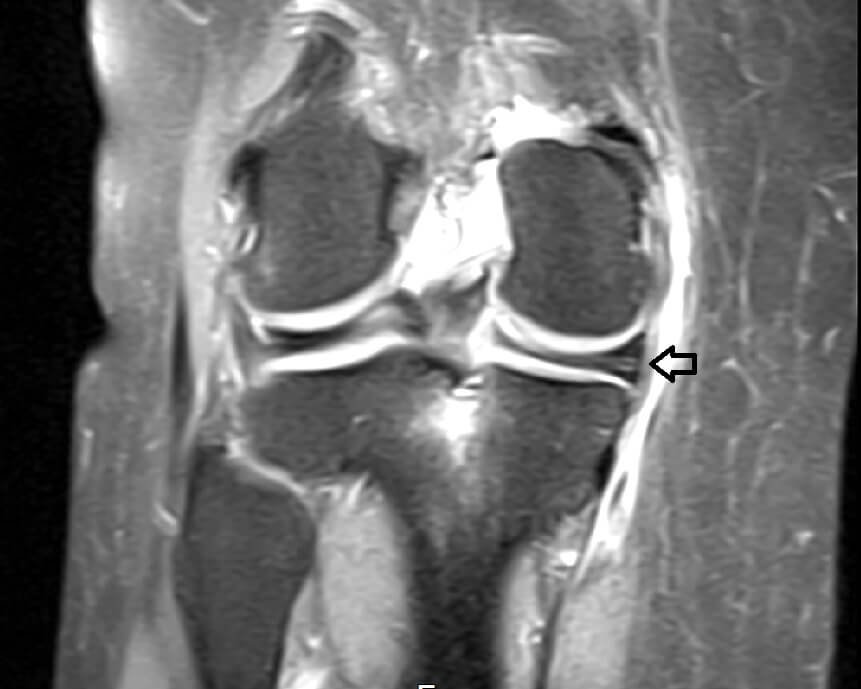

Knee Conditions GET IN TOUCH Knee Arthritis Meniscal Tears ACL Tears Knee Instability The Painful Or Failing Knee Replacement Knee Arthritis Learn MOre Meniscal Tears Learn MOre ACL Tears Learn MOre Knee Instability Learn MOre The Painful Or Failing Knee Replacement Learn MOre KNEE SURGERY OUR SERVICES If joint pain or injury is affecting your daily life, Dr Paterson is here to support your recovery with individualised, evidence-based care. Knee Arthritis Learn MOre Meniscal Tears Learn MOre ACL Tears Learn MOre Knee Instability Learn MOre The Painful Or Failing Knee Replacement Learn MOre OTHER TREATMENT OPTIONS